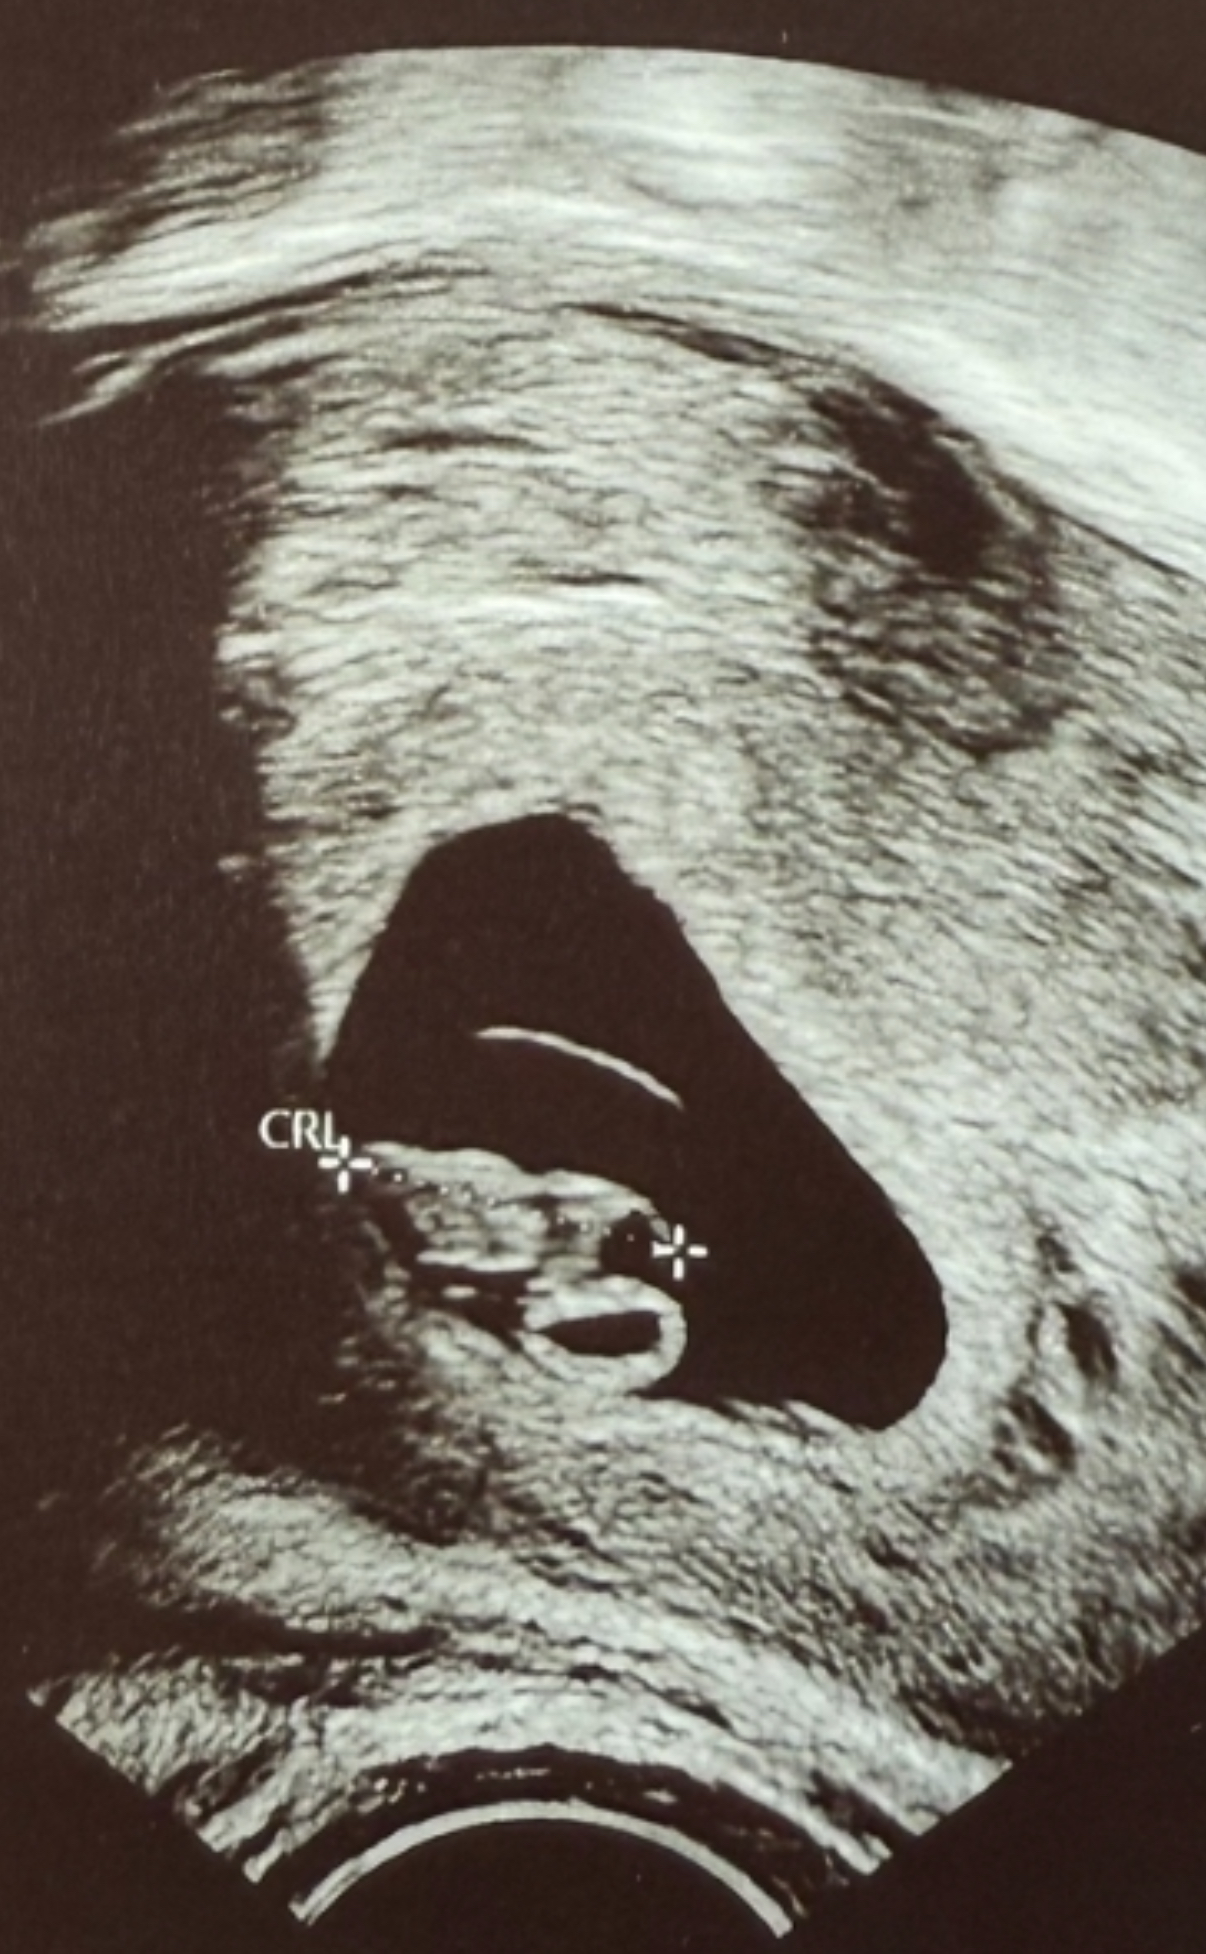

Skal ta en til hcg på fredag også. Har også UL snart, så da håper jeg på å få se en liten levende spire.Nedtelling første UL: 7 dager